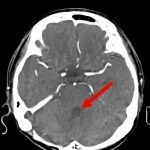

断層撮影

手術前1